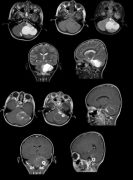

毛细胞星形细胞瘤约占全部儿童脑肿瘤的25%。在磁共振成像中,毛细胞星形细胞瘤通常是一种界限清楚的病变,通常具有囊性和结节状成分,可不均一地增...

毛细胞星形细胞瘤 是一种生长缓慢、边界较清的囊性星形肿瘤,是一种 良性胶质瘤 病理分型,WHO I级。 发病特点 毛细胞星形细胞瘤常发生于儿童和年轻人...

毛细胞星形细胞瘤,俗称毛星,是一种生长缓慢、边界明显、可伴囊性特点的良性肿瘤,WHO I级,好发于儿童和年轻人。毛星好发部位包括:1.视神经;2.视交...